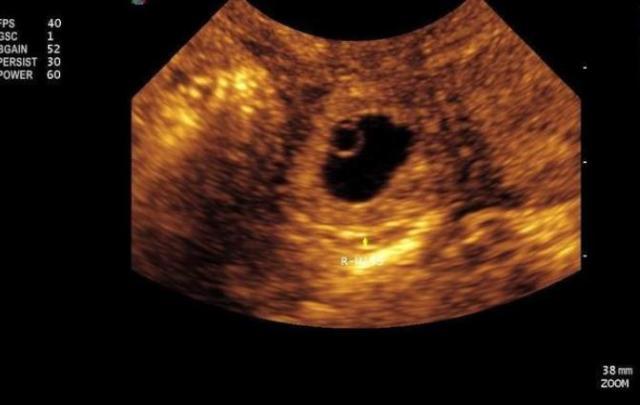

在胚胎发育60天左右孕妈妈要做第一次胎检,主要检测胎囊、胎心、胎芽的情况是否正常,所以首次孕检很重要,也是孕妈妈们最为紧张的一次检查,害怕检查结果不好,担心胎宝宝的健康。

小琪进去的时候还是笑容满面,可是从B超市出来之后愁眉紧锁,老公看到之后赶紧跑过去,这个时候小琪终于忍不住,“医生说,宝宝没有胎心,胎芽,得提前做好心理准备,不过暂时先不急,回家以后静养以后星期之后再来检查,如果到时候还没有胎心胎芽,可能就要做最坏打算了”。

在生活中像小琪这样的例子还是挺多的,有的孕妈刚开始怀孕的时候宝宝没有胎心胎芽,有的甚至2个多月才监测到胎心胎芽,所以说有时候宝妈怀上了不见的就成功了,只有监测出宝宝的胎心胎芽之后才能说肚中的宝宝才有生存的可能。